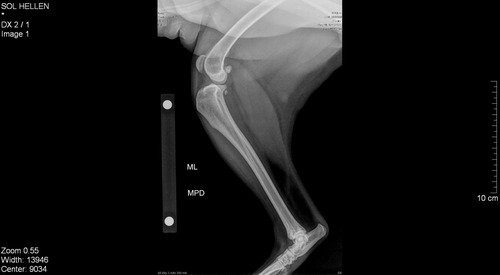

Abaixo está as imagens do raio X dela.

Ruptura de ligamento do joelho, correção cirúrgica, não há outro tratamento, sem isso o animal vive com dor crônica pois vai lesionar os meniscos, alta chance de artrose se desenvolver mais rápido e vai forçar a outra pata pra acontecer a mesma coisaA cirurgia pra corrigir isso chama TPLOValor estimado a vista 2700Material 550Anestesia 650Cirurgia 1500